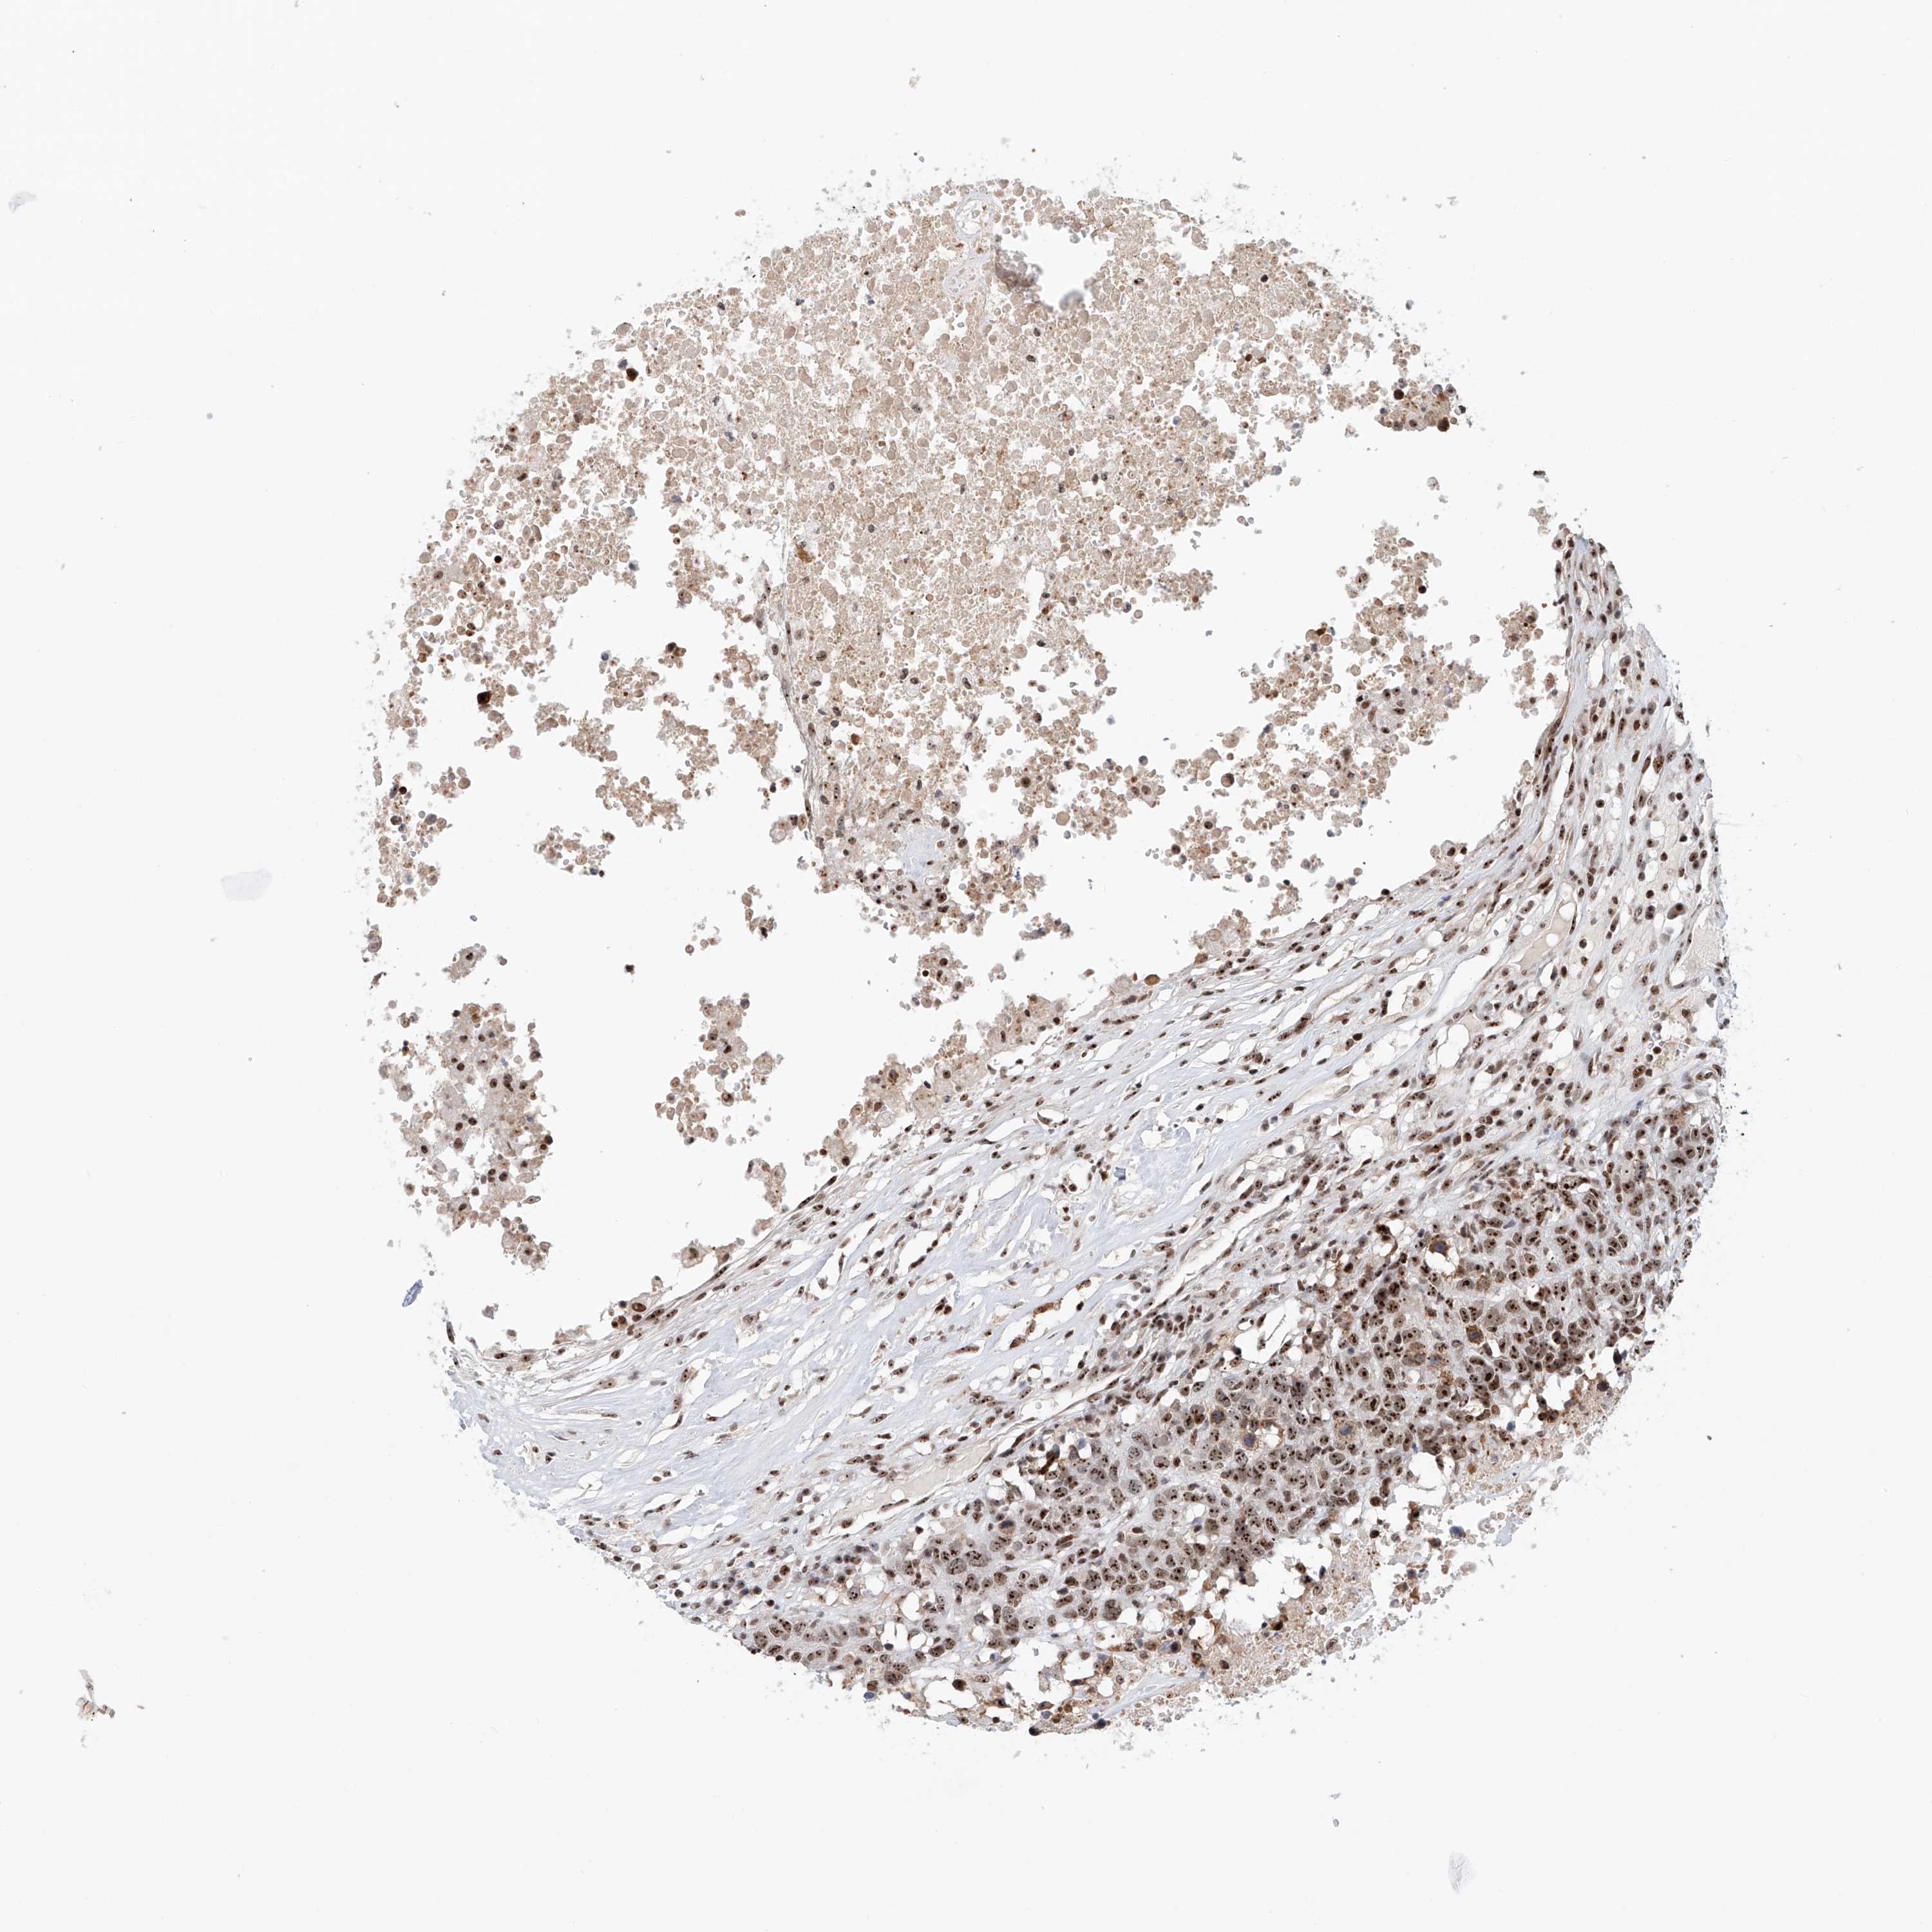

HEAD AND NECK CANCER - Protein expressioni

A mouse-over function shows sample information and annotation data. Click on an image to view it in a full screen mode. Samples can be filtered based on level of antibody staining by selecting one or several of the following categories: high, medium, low and not detected. The assay and annotation is described here.

Antibody stainingi

Antibody staining in the annotated cell types in the current human tissue is reported as not detected, low, medium, or high, based on conventional immunohistochemistry profiling in selected tissues. This score is based on the combination of the staining intensity and fraction of stained cells.

Each image is clickable and will lead to virtual microscopy that enables deeper exploration of all samples and also displays staining intensity scores, fraction scores and subcellular localization as well as patient and tissue information for each sample.

Antibody HPA031079

Staining

High

Medium

Low

Not detected

Intensity

Strong

Moderate

Weak

Negative

Quantity

>75%

75%-25%

<25%

None

Location

Nuclear

Cytoplasmic/membranous

Cytoplasmic/membranous,nuclear

Squamous cell carcinoma, metastatic, NOS